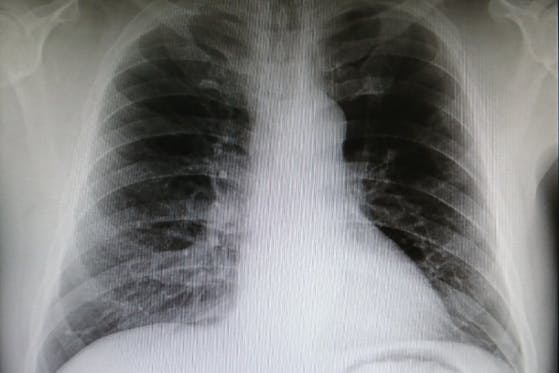

既卒者の診療放射線技師国家試験合格率は、非常に低くため、診療放射線技師になりたいという夢を持っている人に対して、手助けをしたい。理学療法士、柔道整復師の方の画像...